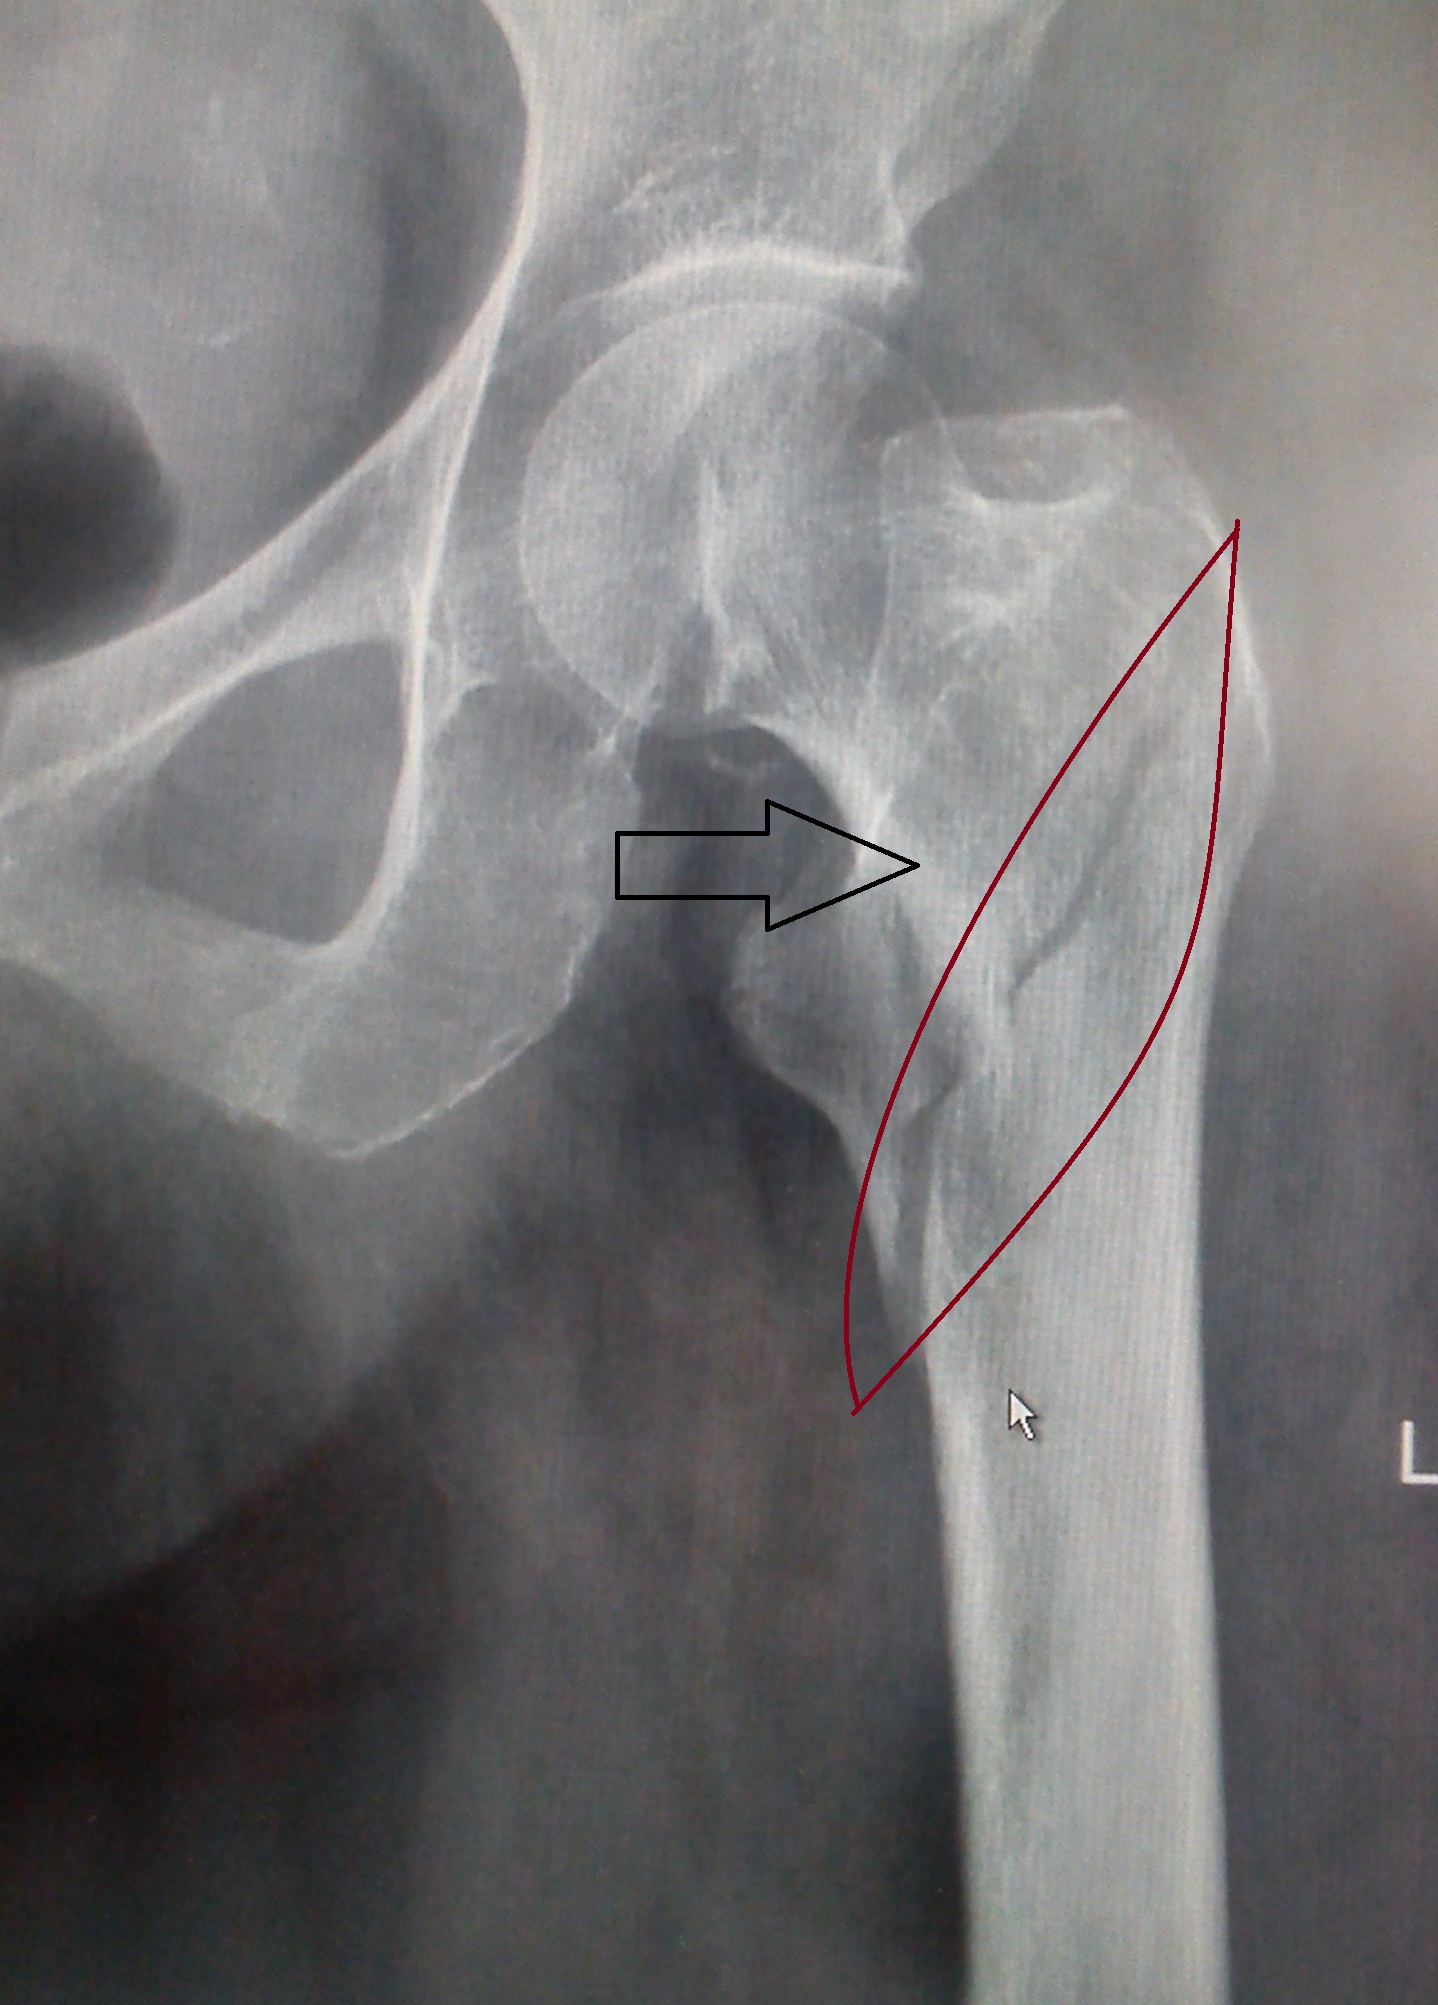

Классификация переломов диафиза бедренной кости: Иллюстрации и информация